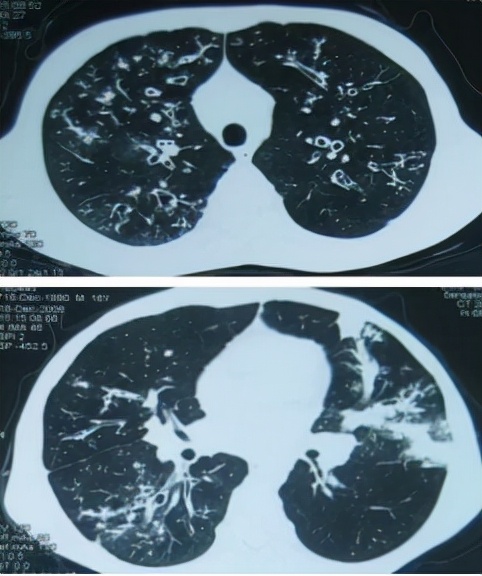

案例看这里27岁的男性患者陈先生 , 反复咳嗽、咳痰4年余 , 四肢消瘦 , 加重伴发热 , 入院时有急性感染的过程 。 胸部CT可见 , 双肺弥漫性支气管扩张 , 左肺出现指套征 , 有片状渗出 , 是很典型的支气管扩张 。

陈先生CT表现图